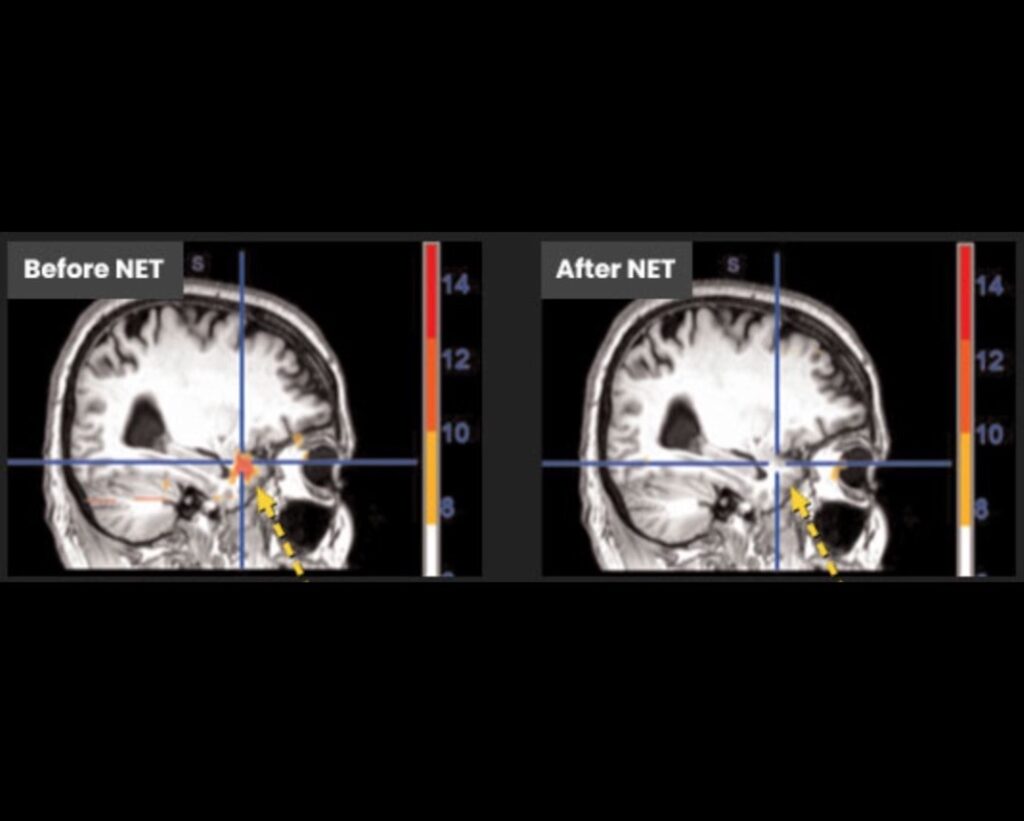

THE SCIENCE BEHIND NET

• Neuroscience (how the nervous system stores and releases stress responses)

It was once believed that stress and emotional responses only lived in the brain. We now know that’s not true. Your entire body experiences and stores emotional responses: your gut, your heart, your muscles, your connective tissue. When stress becomes “stuck,” it alters your physiology in measurable ways.

NET works with this understanding directly. Rather than trying to change your thoughts ABOUT the experience (talk therapy), we work with your body’s physiological response TO the experience.

The result: Your nervous system updates its programming. The old protective pattern gets replaced with a more accurate read of your current reality.